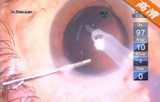

该手术在10点钟位透明角膜主切口制作,前房注入粘弹剂,2点钟位侧切口制作,撕囊镊做连续环形撕囊,做水分离和水分层 ,预吸晶状体皮质 ,超乳劈核法劈核,并逐块乳化吸除核块以及皮质,I/A吸除残留的皮质并对后囊膜进行抛光,前房及囊袋注入粘弹剂,植入爱尔康多焦人工晶状体,吸除前房以及人工晶状体后的粘弹剂。